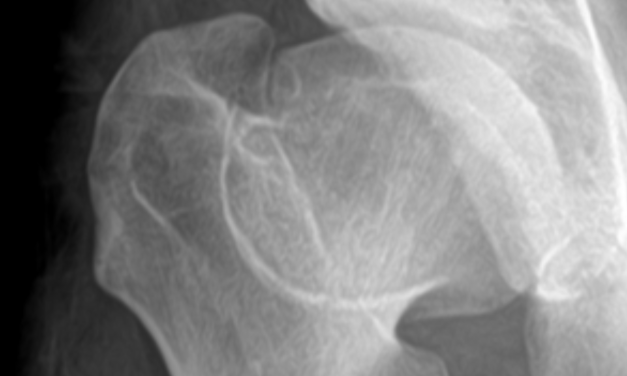

Atypical Proximal Femoral Fracture: An Important Diagnostic Consideration for Patients With Hip, Groin, Or Thigh Pain

Explore the intricacies of hip pain in individuals taking bisphosphonates, uncovering the lesser-known atypical proximal femoral fracture as a potential cause. Dive into the article for a deeper understanding!